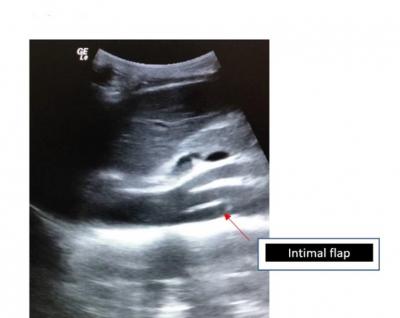

Figure 1: Bedside USG Abdomen in ED shows visualization of an intimal flap (red arrow)

intimal flap